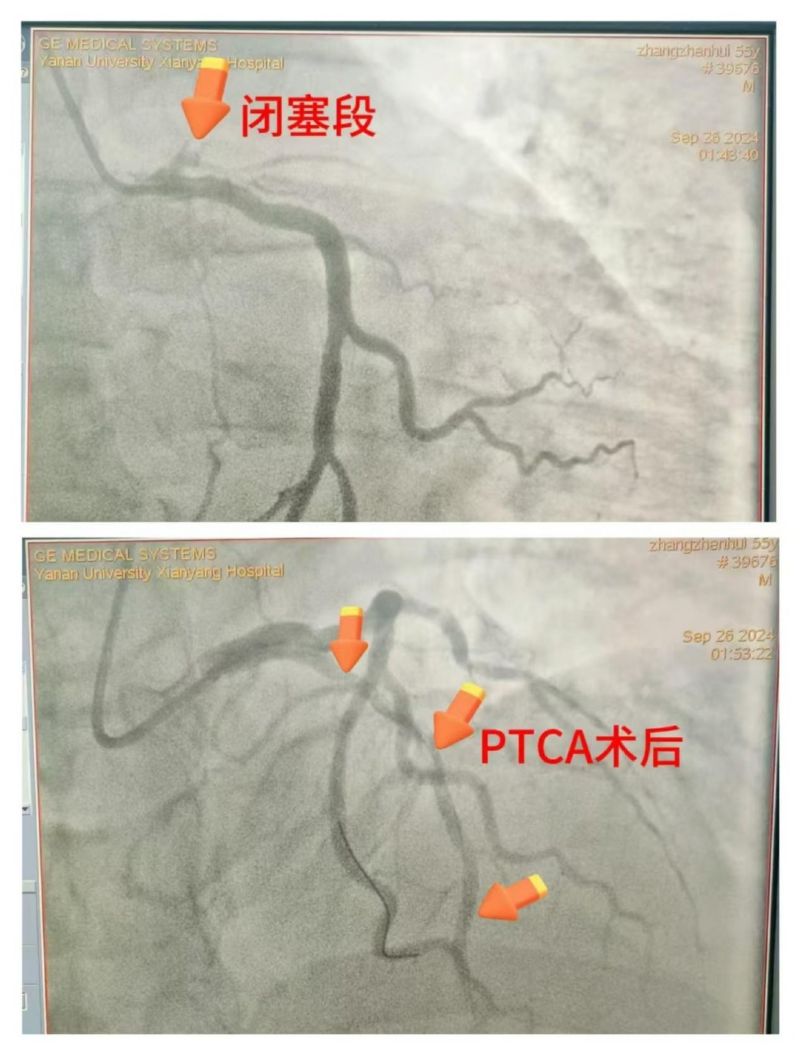

患者仍反復室顫,考慮與急性心肌梗死、急性胰腺炎導致的電風暴相關,唯一的希望是開通罪犯血管,但手術風險極高。李新國科主任與患者家屬充分溝通病情,家屬理解并配合一切治療方案。立即開通胸痛綠色通道,啟動導管室行急診冠脈造影,術中證實為左前降支近段100%閉塞,緊急行PTCA開通罪犯血管,患者心律逐漸穩定,血壓回升,意識好轉,刺激有反應,返回CCU繼續治療。